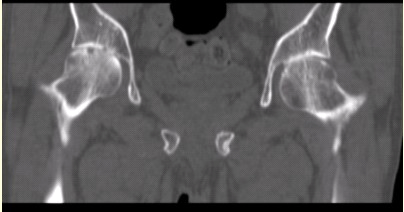

患者女,53岁,双髋关节痛。双髋关节CT平扫冠状重组影像如下图。

可能的诊断为()

A.右侧股骨头缺血性坏死,左髋关节退行性变

B.双髋关节退行性变

C.双髋关节类风湿性关节炎

D.强直性脊柱炎累及双髋关节

E.右髋关节退行性变,左髋关节未见异常

F.双髋关节结核性关节炎

G.双髋关节滑膜炎

本题答案:C, D

髋关节类风湿性关节炎的表现包括()

A.关节间隙均匀性狭窄

B.关节边缘骨赘形成

C.关节周围骨质疏松

D.股骨头轴向移位

E.关节表面骨侵蚀

F.关节腔滑膜增生

G.MRI动态增强检查可以判断病变的活动性

H.关节面下增生、硬化

本题答案:A, C, D, E, F, G

根据影像学,应诊断为(提示CR、MRI结果如下图。)()

F.双髋关节滑膜炎

点击查看答案

本题答案:C, F

对定性诊断有价值的征像包括()

A.双髋关节间隙对称性均匀狭窄

B.右侧股骨头关节面可见小囊状透亮影

C.双髋关节骨质疏松

D.双髋关节未见骨赘

E.双髋关节囊肿胀

F.双髋关节面下无骨质硬化

本题答案:A, C, D, F